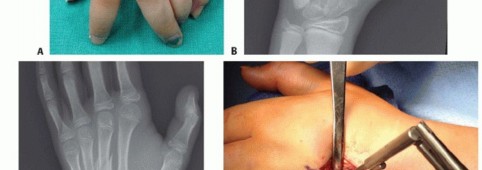

TECH FIG 1 • A. Retrograde (collateral recess) pinning. B,C. Angled distal metacarpal fracture. (continued)

TECH FIG 1 • (continued) D,E. Fracture stabilized with two pins that have been advanced to the base of the metacarpal. (Copyright Thomas R. Hunt III, MD, DSc.)